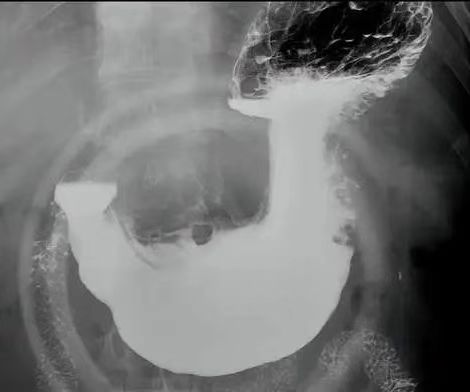

消化道造影全称为X 线气钡双重对比造影,核心原理是利用钡剂(高密度)与空气(低密度)的对比,通过 X 线摄片呈现消化道壁的形态、轮廓及功能状态。检查时患者需口服钡剂(有时需加服产气粉),在不同体位下,医生通过 X 线机捕捉食管、胃、十二指肠及结肠的充盈、黏膜和排空影像,判断是否存在溃疡、肿瘤、狭窄等结构异常。

病变检出率:目前研究显示,胃镜对消化道疾病的敏感性为 88%,气钡造影为 86%,但两者联合可提升至 93.2%。具体到细分病变:

消化道造影对食管憩室(检出率 0.73% vs 胃镜 0.15%)、管壁僵硬等结构改变的识别更具优势。